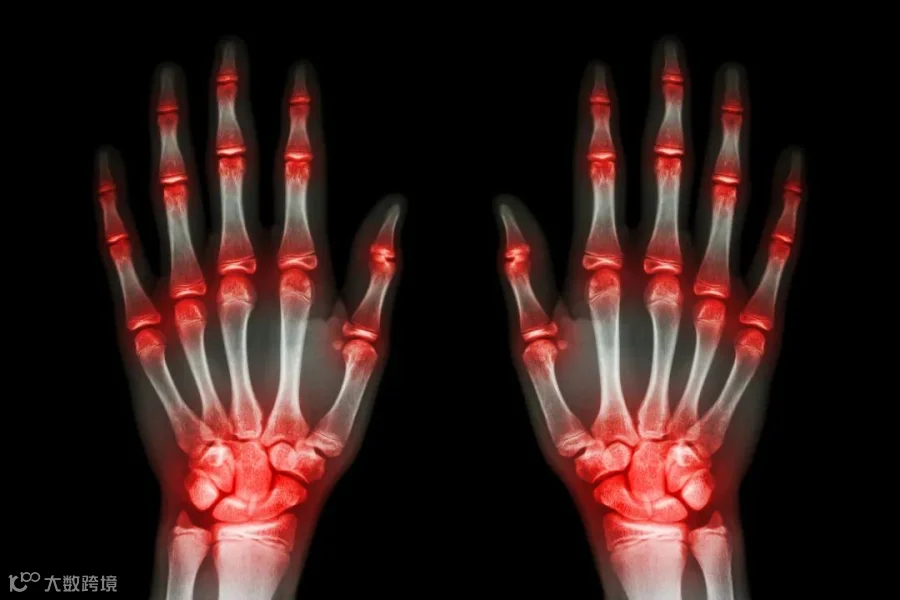

类风湿关节炎是常见的以关节组织慢性炎症性病变为主要表现的自身免疫性疾病,女性患者多见,与男性患者的患病比例为3:1,女性患者高发年龄为45-54岁[2]。

发病时患者可出现关节对称性症状,如疼痛、晨僵、红肿灼热、活动受限等,同时还可出现疲劳、肌无力、食欲减退、体重减轻、低热等等全身症状。